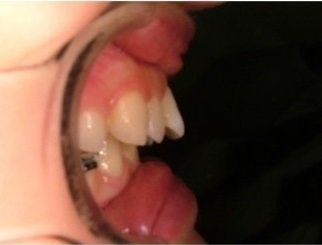

L'idea innovativa di applicare delle maniglie (brackets) sul lato interno dei denti, rivolto alla lingua anziché sul lato esterno rivolto al labbro ed esposto al sorriso, ha fatto sì che questa tecnica venisse denominata “linguale".

Il trattamento ortodontico non rappresenta più una preoccupazione di inestetismo del sorriso durante il trattamento, ma anzi permette di apprezzarne gli avanzamenti sin dall’inizio. Il lieve imbarazzo fonetico dovuto all'interferenza dei brackets con la lingua viene superato in pochi giorni di adattamento, e solo in casi rari può richiedere fino a un mese.